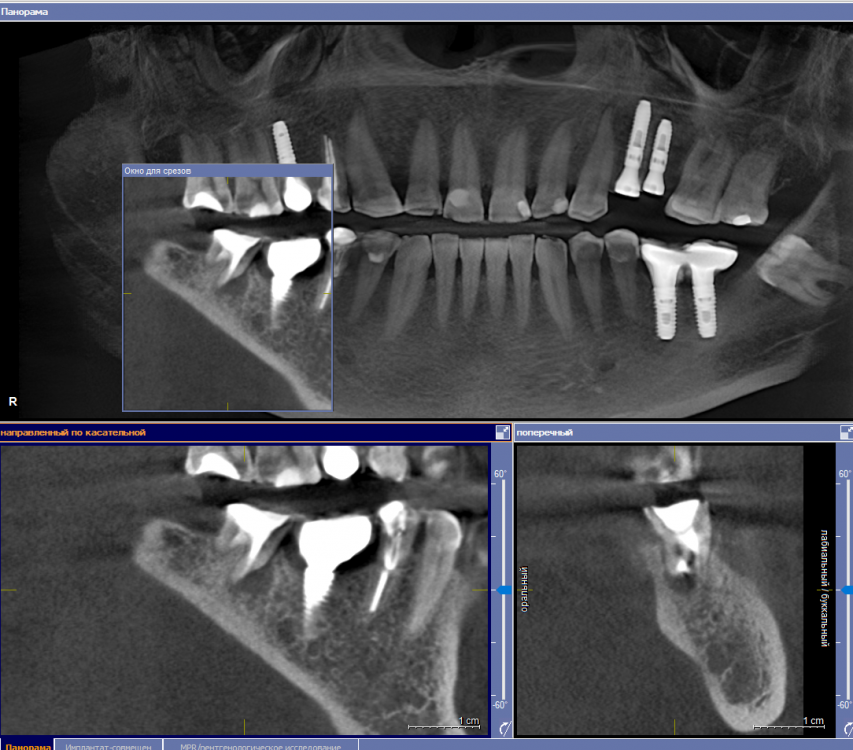

se77777 Опубликовано 3 апреля, 2023 Автор Поделиться Опубликовано 3 апреля, 2023 Здравствуйте, проведена одномоментная имплантация. Спустя 5 месяцев поставлена коронка. Коронка стоит месяц. На третьем месяце после имплантации стала беспокоить боль в плече, списывал на перенесенный COVID-19. Было субъективное ощущение, что температура формирователя повышена по отношению к остальным зубам и к формирователям, которые носил прежде. На днях стали беспокоить тянущая неинтенсивная боль в челюсти со стороны импланта. КТ сделана полтора месяца назад. Ссылка на комментарий

red_butler Опубликовано 3 апреля, 2023 Поделиться Опубликовано 3 апреля, 2023 Здравствуйте, срезы кт выставлены не правильно. Покажите еще Ссылка на комментарий

se77777 Опубликовано 3 апреля, 2023 Автор Поделиться Опубликовано 3 апреля, 2023 (изменено) Пожалуйста, дайте ссылку, как правильно выставлять срезы. Изменено 3 апреля, 2023 пользователем se77777 Загрузка изображений Ссылка на комментарий